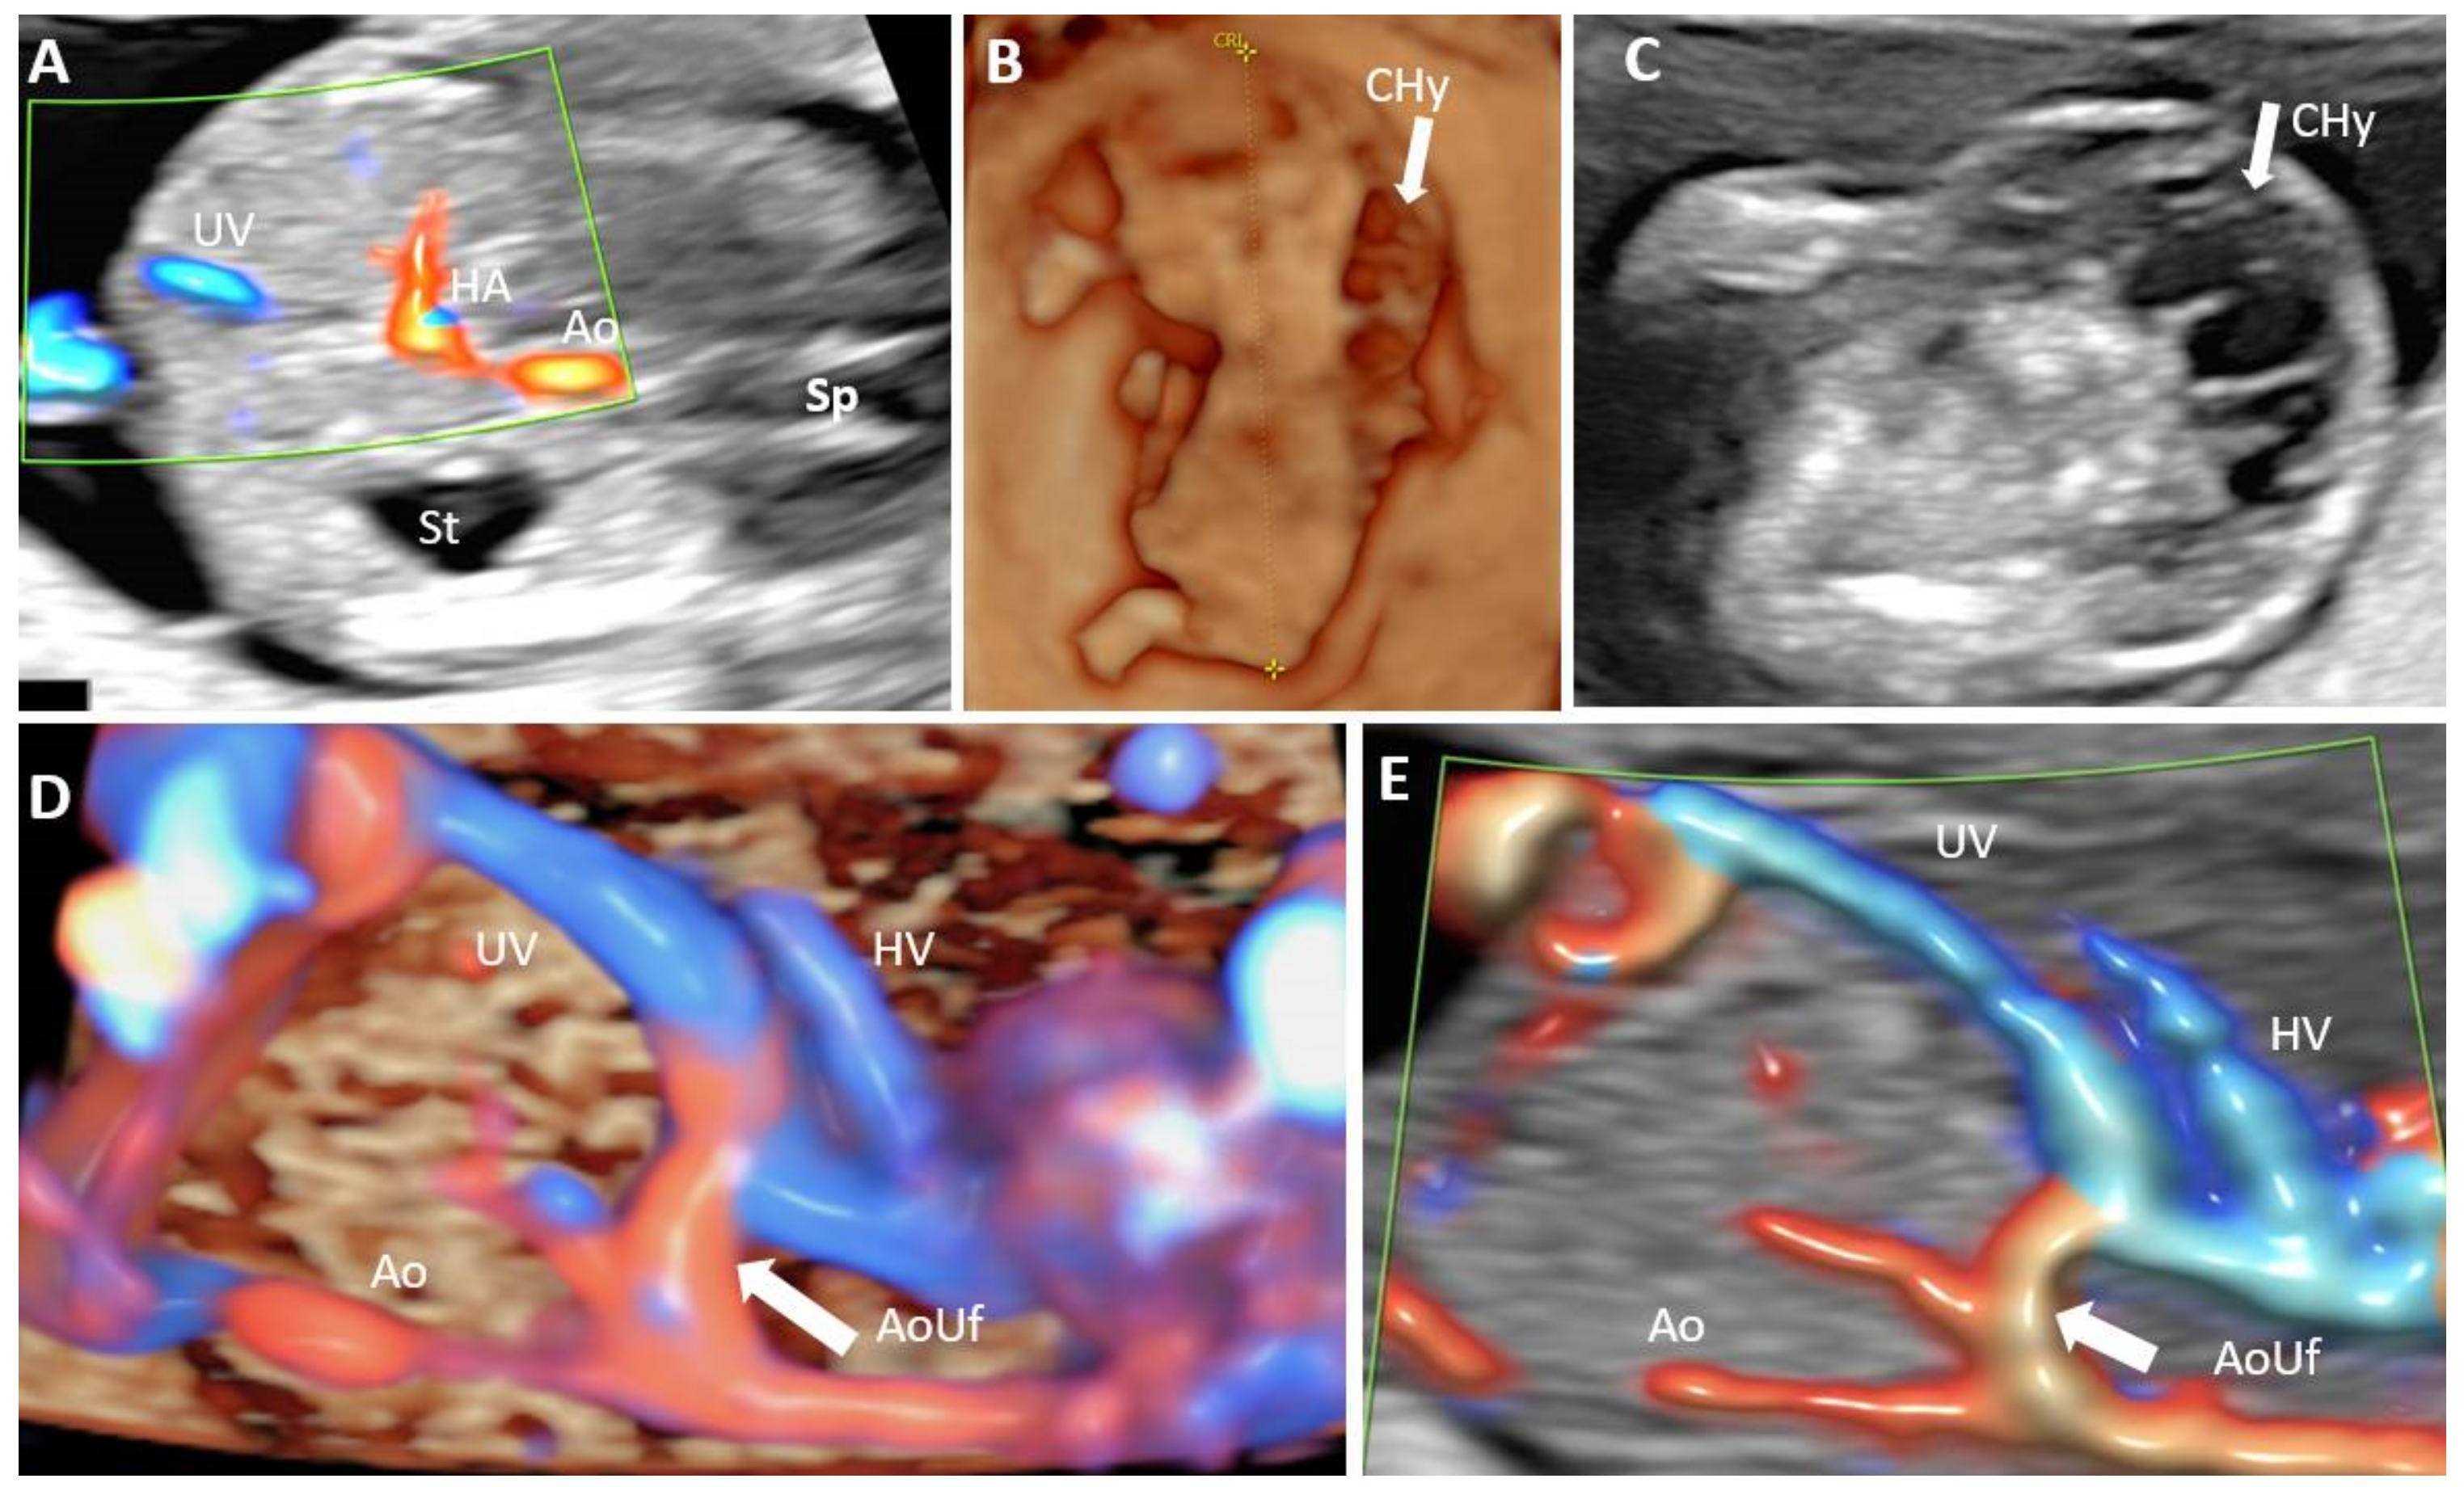

- Achiron, R.; Kivilevitch, Z. Fetal umbilical-portal-systemic venous shunt: In-utero classification and clinical significance. Ultrasound Obstet. Gynecol. 2016, 47, 739–747. [Google Scholar] [CrossRef] [Green Version]